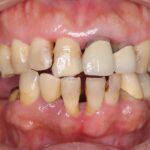

左上の2番が隠れていてすきっ歯に見える

インビザライン(全体矯正)+ホワイトニングコースの症例

歯の裏に歯が隠れてしまっていた久米さんも、全体矯正(非抜歯+遠心移動)で美しく改善。

・費用:935,000円(税込)

・治療期間:30ヶ月

・通院回数:30回

・35歳女性

-リスクと副作用-

・長時間マウスピースを装着するため、むし歯や歯周病のリスクがある。治療後はリテーナーを装着しないと後戻りしてしまうリスクがある。

・ホワイトニング剤の影響で知覚過敏が起こる可能性がある。色が徐々に戻る可能性がる。